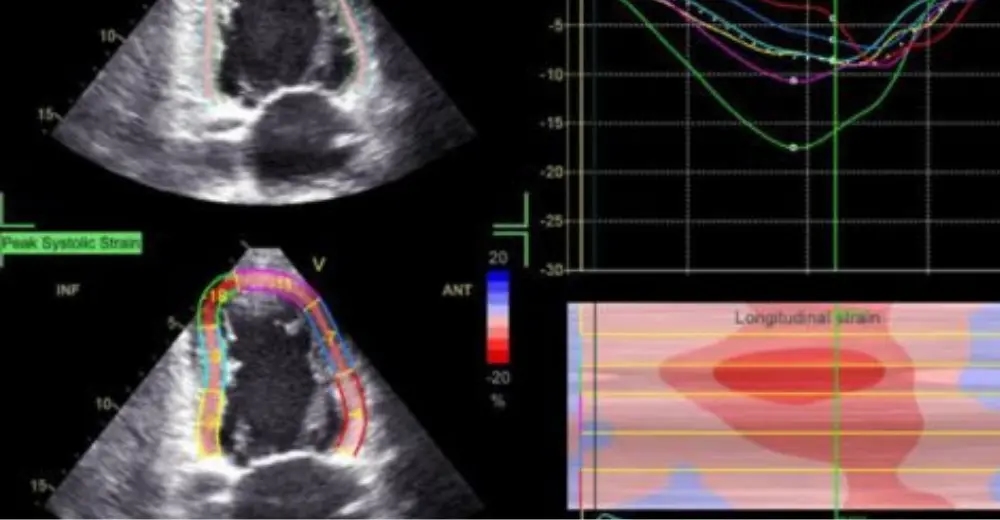

📈 How is the result presented?

The most commonly assessed global longitudinal strain (GLS) of the left ventricle. The mathematically processed result is presented in the form of a 16- or 17-segment diagram (bull's eye), graphs and GLS values obtained from three different slices (LAX, A2Ch, A4 Ch) and the average GLS value